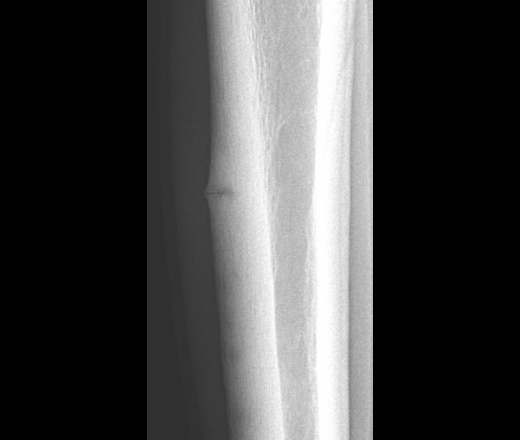

Рис. 1. Лоозера зона перестройки в корковом слое большеберцовой кости в виде полоски разрежения, имитирующей неполный перелом (обозначена стрелкой).

Рис. 3. Лоозера зона перестройки диафиза большеберцовой кости, напоминающая картину коркового абсцесса.

Пациент 1994 года рождения, занимается профессионально борьбой, в течение месяца беспокоят боли по передней поверхности большеберцовой кости с появлением локального участка уплотнения. Кожа не гиперемирована и не отечна. Травму отрицает.Первый раз столкнулся с такими структурными изменениями, надеюсь на Вашу подсказку уважаемые коллеги. Заранее спасибо.

Еще один случай перестройки костной ткани в большеберцовой кости.

в области проксимального метадиафиза большеберцовой кости.

Подростки-близнецы направлены на рентгенологическое исследование с жалобами на боль в верхней трети большеберцовой кости справа, связанные с большими физическими нагрузками, припухлость, нарушение функции правой нижней конечности. На рентгенограммах костей голени в верхней трети правой большеберцовой кости определяется деформация в виде утолщения кортикального слоя с признаками линии перелома (рисунок 4,5).